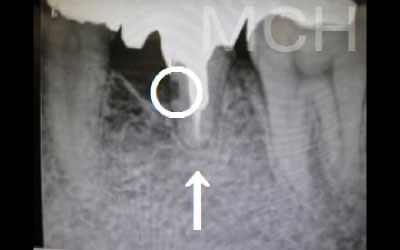

骨が薄い状態では、そのままインプラントを行うのはおすすめできません。

しかし、事前に骨を増やす処置を行ったり、インプラント埋入と同時に骨造成を行うことで、インプラント治療は十分に可能です。

顎の骨の中には神経が通っており、インプラント治療の際にそれを傷つけてしまうリスクがあります。

しかし、当院では事前にCT撮影を行い、神経までの距離を三次元的に正確に把握した上で治療計画を立てるため、リスクをしっかり回避できます。

さらに、骨を削りすぎないようにするための専用のストッパーも導入しており、安全性には十分に配慮しています。

今回のご質問ですが、抜けた部分の骨が薄いなどの理由で「インプラントはできない」と言われた可能性があります。

前歯はもともと骨が薄く、歯が抜けると時間の経過とともにさらに骨が痩せてきてしまうので、インプラント治療の難易度が高い場所です。

ただ結論からお話すると、インプラント治療は可能です。

なぜなら、もし仮に骨が薄くても、骨の治療によって厚みが増せば、安全にインプラント治療が行えるからです。

1)インプラント治療を行う前に、骨の治療が必要かもしれません。

4)骨の状況をしっかり把握するためにも、CT撮影が必須となります。